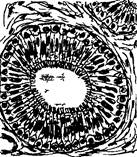

Рис. 4. Поперечный разрез канальцев нефрона

1 - извитой канадец 1-го порядка (проксимальный каналец); 2 - извитой каналец 2-го порядка (дистальный каналец); 3 - тонкая часть петли Генле; 4 - капилляр.